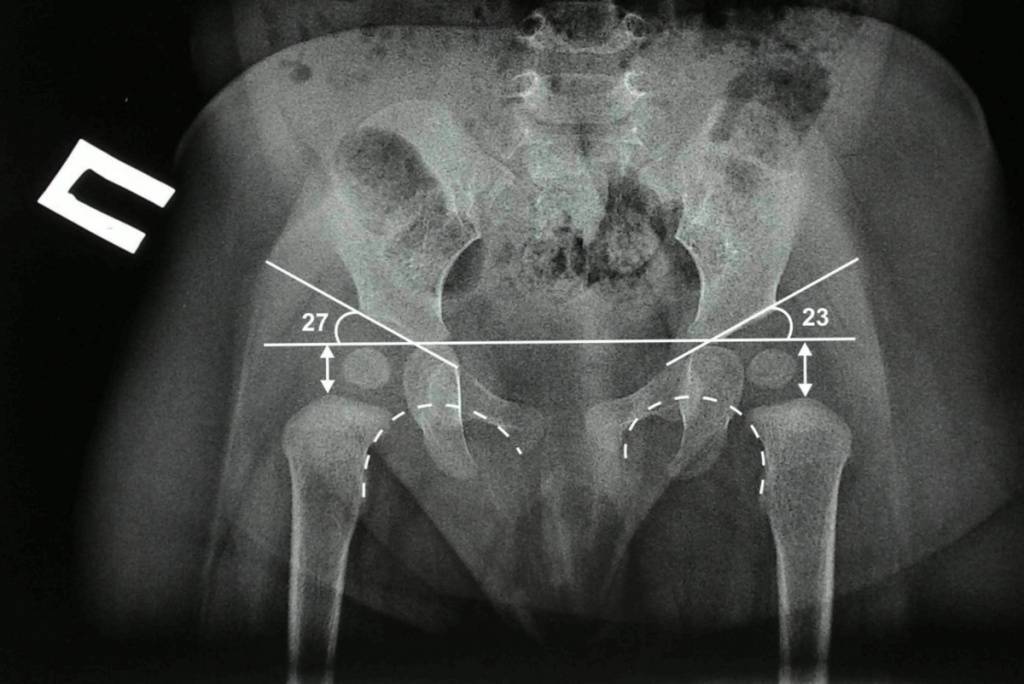

Рентгенологическая диагностика

У новорожденных вертлужная впадина и большая часть бедренной головки представлены хрящевой тканью, поэтому на рентгенологических снимках не видны. Для трактовки результатов используют различные схемы с проведением специальных линий, чтобы рассчитать угол наклона крыши вертлужной впадины. В норме он должен быть не меньше 30° у новорожденных и примерно 20° – у малышей от трех месяцев и старше.